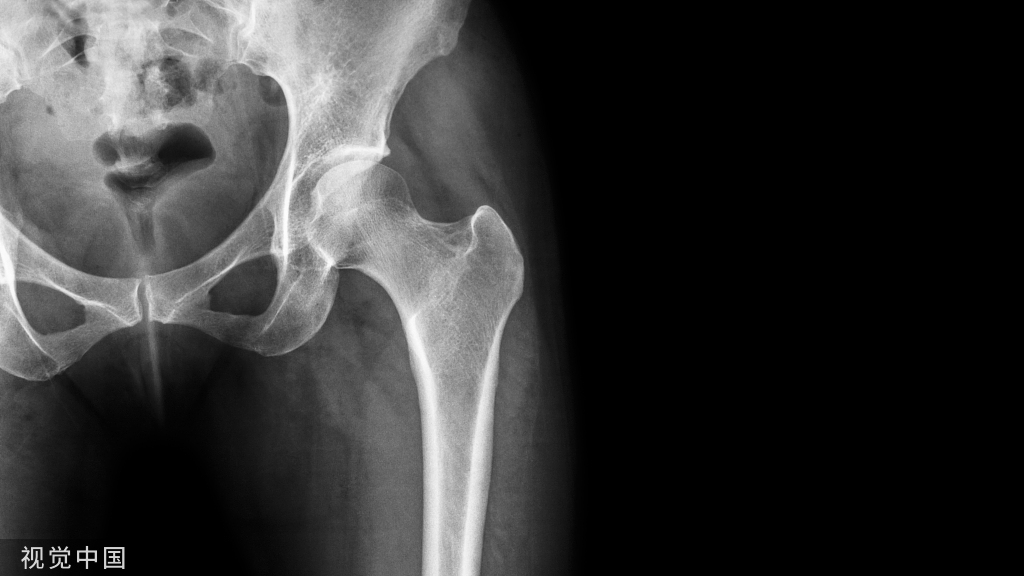

# 骨关节炎退行性(结果,非症状):

弹响低钝且频仍,响声发自骨外侧的髌股关节,同时伴关节肿胀,偶有交锁征象。MRI可看到关节退变,半月板呈“孤岛样”。关节镜下可看到关节软骨及半月板退变、骨质增生压迫韧带和关节囊。

# 髌股关节紊乱先赋性

平常见于支撑带挛缩、髁浅平、高/低位髌骨者。膝前弹响,声音清脆或低钝,频率高,伴有摩擦感或捻发音,髌骨勾当度差,髌周有压痛,研磨及阴抗试验都呈阳性。轴位片可以表示髌股关节适配差,正位片可以看到高/低位髌骨。关节镜可看到髌骨外倾或半脱位较多见,髌股关节面有软骨退变。